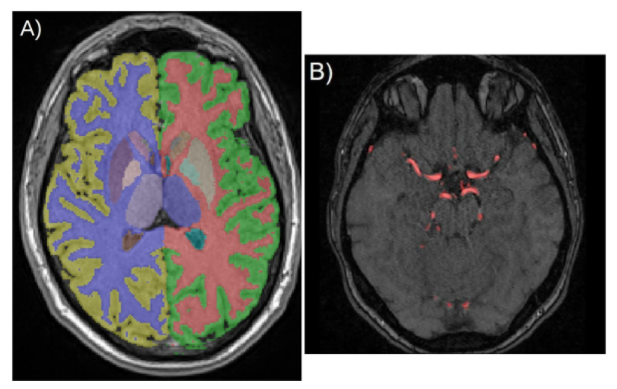

Healthy brain aging leads to morphological changes in the cortical, subcortical and vascular structures of the brain. Several changes are also associated with neurological diseases such as Alzheimer’s diseases. Understanding better these changes is important to be able to differentiate pathological versus normal aging at an early stage. To this aim, we use brain magnetic resonance imaging (MRI) and angiography (MRA) from healthy adults and either use extracted features, such as volumes, or the raw images, to quantify and visualize the impact of aging and additional clinical and life behavioral factors on the brain.